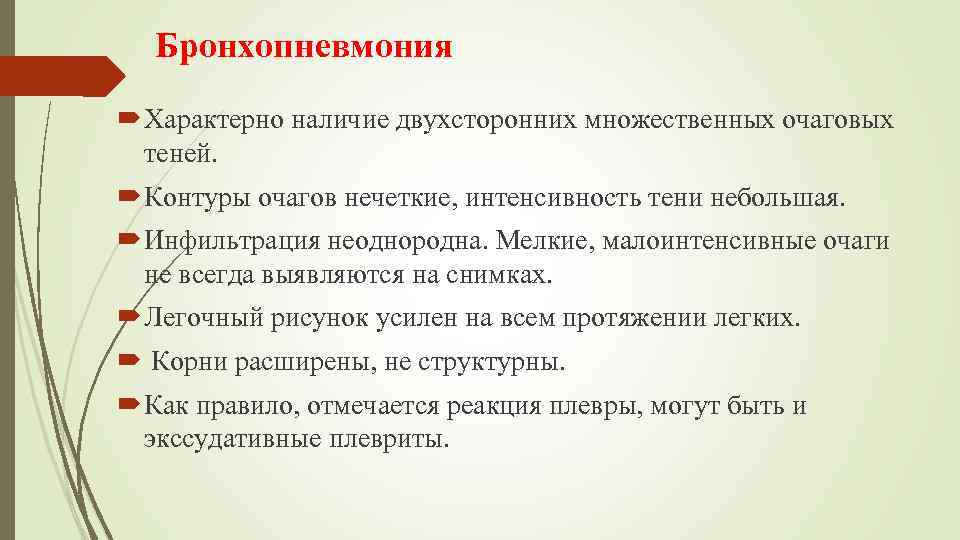

Бронхопневмония Характерно наличие двухсторонних множественных очаговых теней. Контуры очагов нечеткие, интенсивность тени небольшая. Инфильтрация неоднородна. Мелкие, малоинтенсивные очаги не всегда выявляются на снимках. Легочный рисунок усилен на всем протяжении легких. Корни расширены, не структурны. Как правило, отмечается реакция плевры, могут быть и экссудативные плевриты.

Бронхопневмония Характерно наличие двухсторонних множественных очаговых теней. Контуры очагов нечеткие, интенсивность тени небольшая. Инфильтрация неоднородна. Мелкие, малоинтенсивные очаги не всегда выявляются на снимках. Легочный рисунок усилен на всем протяжении легких. Корни расширены, не структурны. Как правило, отмечается реакция плевры, могут быть и экссудативные плевриты.